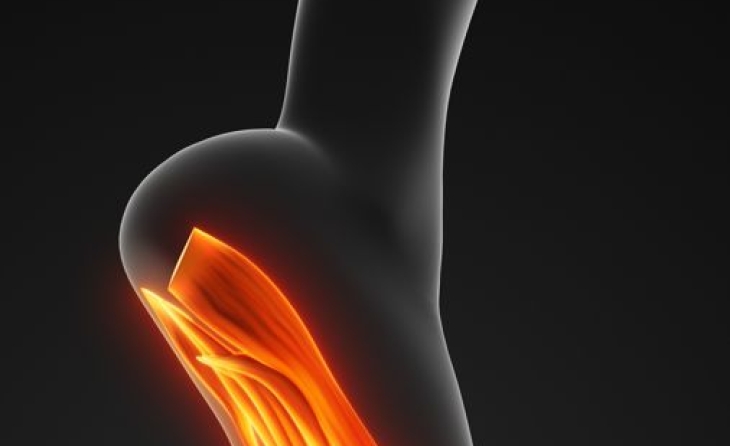

Η ανάπαυση, τα αντιφλεγμονώδη φάρμακα, η εφαρμογή πάγου και οι ασκήσεις αποκατάστασης βοηθούν στον περιορισμό της φλεγμονής. Σε επίμονες περιπτώσεις, όπου μπορεί να υπάρχει και πίεση ενός νευρικού κλάδου, του νεύρου Baxter που βρίσκεται εν τω βάθει της απονεύρωσης, η έγχυση κορτιζόνης με τη βοήθεια του υπερήχου μπορεί να είναι πολύ αποτελεσματική. Επί αποτυχίας της συντηρητικής αγωγής συνιστάται χειρουργική αντιμετώπιση.